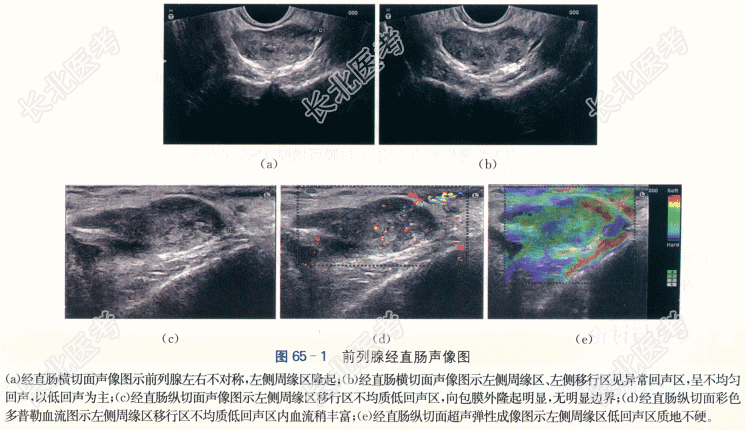

二、影像资料